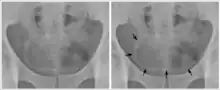

- Cystite et urétérite (S. haematobium) avec hématurie, qui peut évoluer en cancer de la vessie (carcinome épidermoïde) ;

Le cancer de la vessie et la mortalité sont généralement élevés dans les régions touchées.